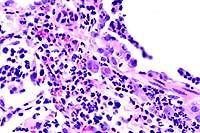

40x

obj.

- Case 22-1. Lung. Alveoli are filled with neutrophils

and lined by type II pneumocytes which occasionally contain eosinophilic

intranuclear inclusions bodies.